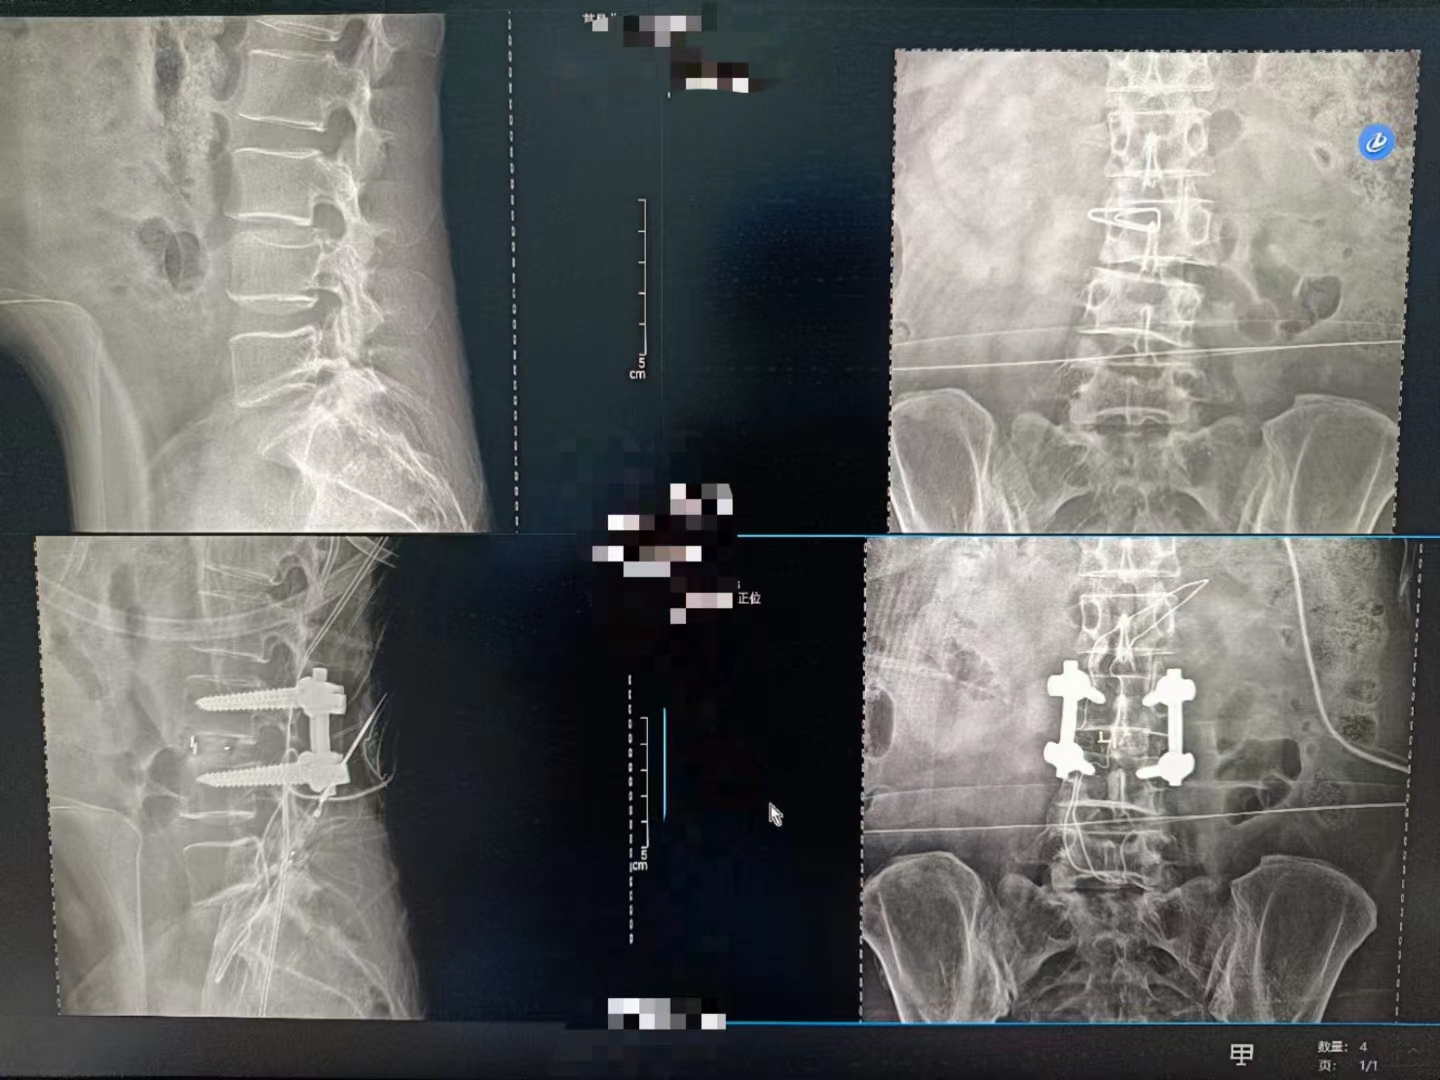

當設備啟動,那束柔和的X射線穿過患者的身體,捕捉下每一個細微的影像。那一刻,時間仿佛凝固,所有的目光都聚焦在那塊屏幕上。那里,生命的紋理清晰可見,疾病的陰影無處遁形。

手術順利完成,當醫生們露出疲憊而欣慰的笑容時,我知道,那不僅僅是勝利的喜悅,更是對生命的敬畏與珍視。而這一切,都離不開這臺數字化X射線攝影設備的默默付出。